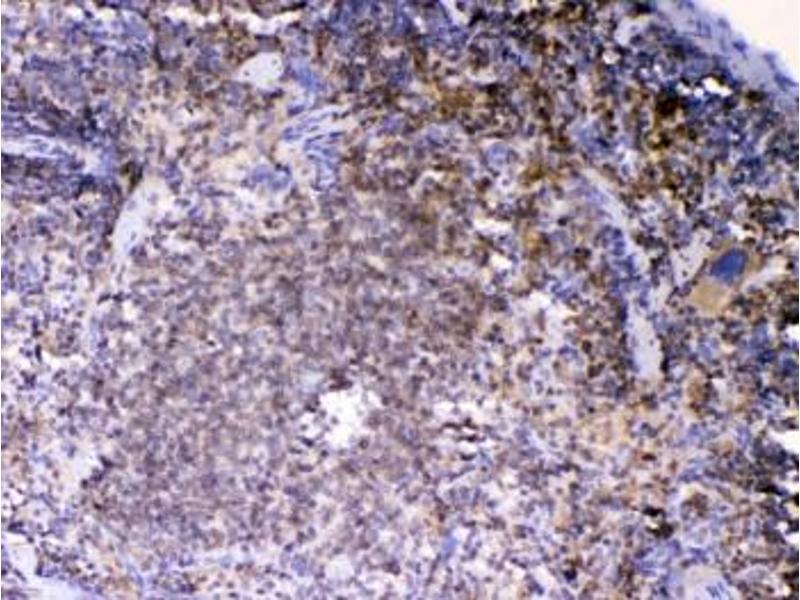

- Optimal dilution of the LYN antibody should be determined by the researcher.\. Western Blot: 0.5-1 μg/mL,IHC (FFPE): 1-2 μg/mL